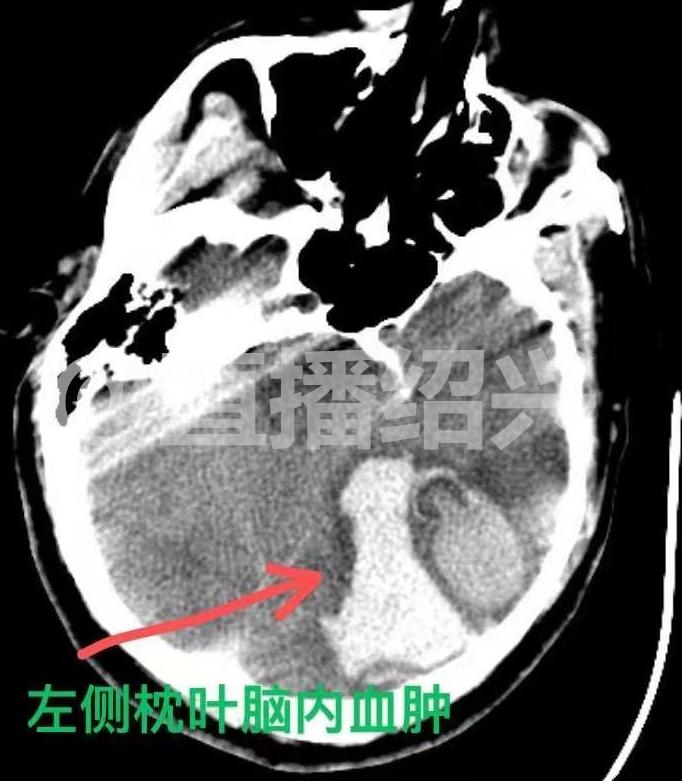

(箭頭所指為出血處)

原來,老吳的工友到中午干完活,發(fā)現(xiàn)老吳還趴在桌上睡覺,才意識(shí)到情況不對(duì)了,工友們連聲呼喊老吳,但老吳已經(jīng)不省人事了,于是大伙連忙撥打了120急救電話把老吳送到了醫(yī)院。老吳的主治醫(yī)師董昌明告訴記者,老吳剛被送到醫(yī)院的時(shí)候,瞳孔已經(jīng)放大了,隨時(shí)可能有生命危險(xiǎn),醫(yī)院立即對(duì)老吳進(jìn)行了手術(shù)。在手術(shù)過程中醫(yī)生發(fā)現(xiàn)老吳腦內(nèi)有大量的畸形血管,其中一條血管甚至長得跟燈泡一樣。術(shù)后,老吳的身體情況依舊不太樂觀,甚至被送進(jìn)了重癥監(jiān)護(hù)室。